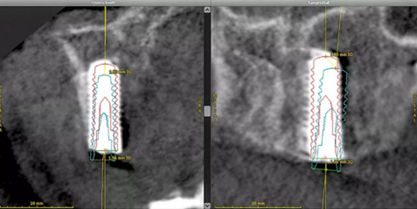

據(jù)有關(guān)文獻(xiàn),在使用CBCT輔助制作種植體導(dǎo)板時(shí),種植體位置偏差為0.43mm,角度偏差4度。粘膜支持式導(dǎo)板誤差為0.7-0.9mm之間,牙支持式外科導(dǎo)板往往表現(xiàn)出更高的精確度。但在該手術(shù)中,平均角度誤差為1.78度,種植體體部和種植體頂端的3D偏置平均值分別為0.63mm和0.89mm,指數(shù)誤差均在所需的范圍內(nèi)。以上數(shù)據(jù)經(jīng)治療評(píng)估工具 (coDiagnostixTM) 檢查得出(圖 12)。

(圖12)